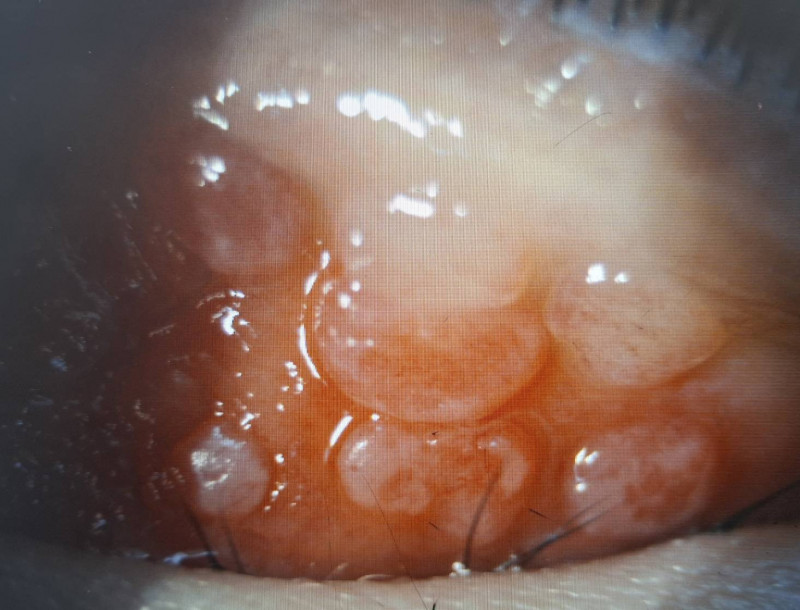

小二男童因長期眼睛癢揉眼,結膜炎導致左上眼瞼出現多顆巨大乳突。(洪啟庭提供)

男童因結膜慢性發炎,使結膜上皮細胞的過度增生,長成大於0.1公分的乳突。(洪啟庭提供)

巨大乳突壓迫不僅造成角膜潰瘍,還出現高度散光而視力模。(洪啟庭提供)

達特楊眼科聯盟執行長洪啟庭指出,小二男童就醫時不僅左眼眼瞼嚴重腫脹,最佳視力僅0.5並有300度散光,應是過敏性結膜炎合併過敏性鼻炎、濕疹、異位性皮膚炎或氣喘等,因為長期揉眼導致眼皮長滿巨大乳突,因長時間壓迫造成上半部角膜有淺層潰瘍,故造成300度的高度散光和視力模糊,經強效抗生素與適當類固醇藥水治療,2星期後角膜潰瘍痊癒,乳突的也變小,學童眨眼睛的現象也明顯改善,但乳突完全消失恐要半年以上。